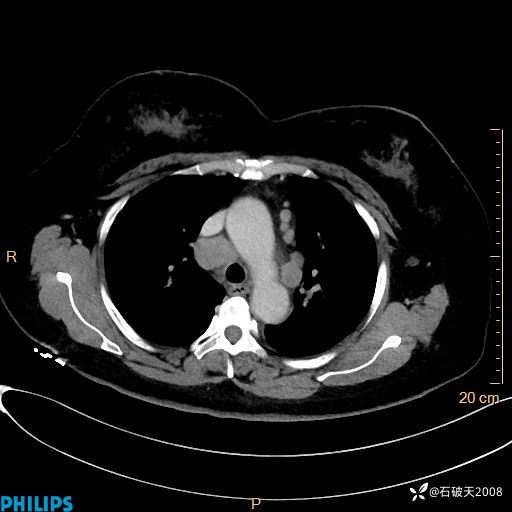

动脉期